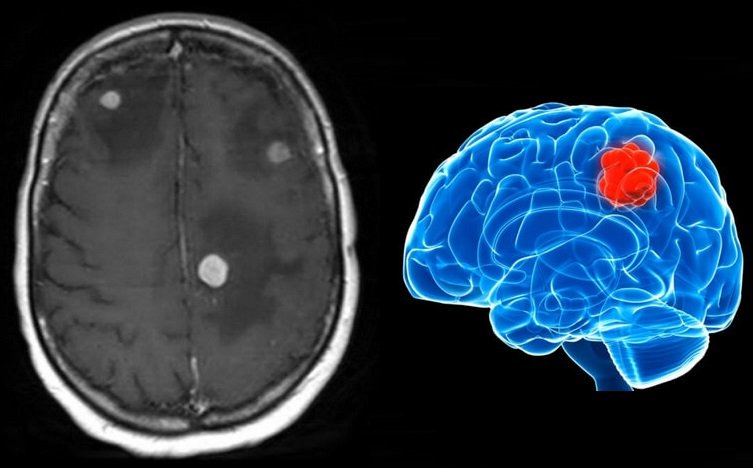

Ressonância Magnética (RM) – Exame de Escolha

Padrão-ouro para diagnóstico de metástases cerebrais

RM com Contraste (Gadolínio):

• Essencial: metástases realçam intensamente

• Identifica número de lesões

• Avalia tamanho e características

• Detecta lesões pequenas não visíveis sem contraste

Características Típicas:

• Lesões arredondadas ou ovaladas

• Localização periférica: junção córtico-subcortical

• Realce anelar: anel captante de contraste

• Edema perilesional: inchaço ao redor (geralmente proeminente)

• Múltiplas lesões: em diferentes localizações

• Hemorragia: comum em melanoma e carcinoma renal